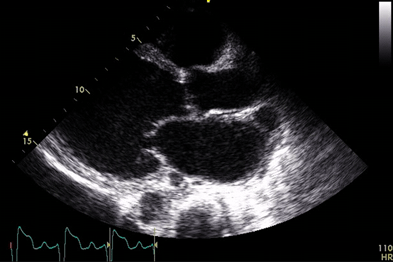

Echo In Cardiomyopathy - Doctor Moody

Echo Features in Dilated Cardiomyopathy •Increased LV diastolic and systolic volumes •Decreased LV systolic function •Increased sphericity (long-axis ... Read Here

DILATED CARDIOMYOPATHY - American Heart Association

DILATED CARDIOMYOPATHY Dilated or congestive cardiomyopathy (DCM) is diagnosed when the heart is enlarged (dilated) and the pumping chambers contract poorly (usually left side worse than right). A diagram and echocardiogram comparing a normal heart ... Return Doc